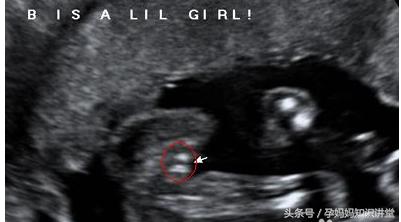

首先,是我们看B超图中是否有三条线,很显然的,如果有三条线存在,那么说明胎儿是女姓,没有则是男娃。

其次,看B超图是否有明显凸出的地方,如果有,而且类似一团菌状,那也很显然,这个胎儿是男性,没有则是女娃。